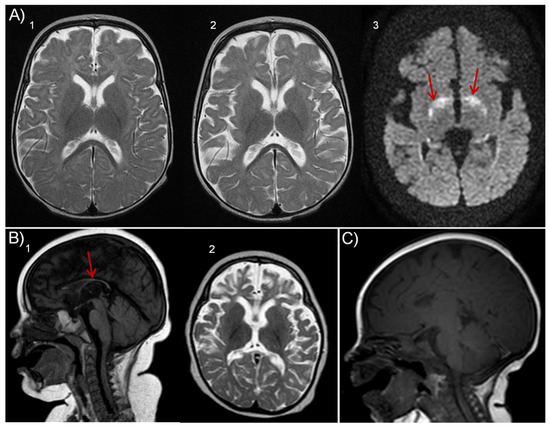

Spinocerebellar Ataxia in a Hungarian Female Patient with a Novel Variant of Unknown Significance in the CCDC88C Gene

by Fanni Annamária Boros, László Szpisjak, Renáta Bozó, Evelyn Kelemen, Dénes Zádori, András Salamon, Judit Danis, Tibor Kalmár, Zoltán Maróti, Mária Judit Molnár, Péter Klivényi, Márta Széll and Éva Ádám

Int. J. Mol. Sci. 2023, 24(3), 2617; https://doi.org/10.3390/ijms24032617 - 30 Jan 2023

Spinocerebellar ataxia (SCA) 40 is an extremely rare subtype of the phenotypically and genetically diverse autosomal dominant ataxias caused by mutations of the CCDC88C gene. Most reported cases of SCA40 are characterized by late-onset cerebellar ataxia and variable extrapyramidal features; however, there is [...] Read more.

Spinocerebellar ataxia (SCA) 40 is an extremely rare subtype of the phenotypically and genetically diverse autosomal dominant ataxias caused by mutations of the CCDC88C gene. Most reported cases of SCA40 are characterized by late-onset cerebellar ataxia and variable extrapyramidal features; however, there is a report of a patient with early-onset spastic paraparesis as well. Here, we describe a novel missense CCDC88C mutation (p.R203W) in the hook domain of the DAPLE protein encoded by the CCDC88C gene that was identified in a female patient who developed late-onset ataxia, dysmetria and intention tremor. To explore the molecular consequences of the newly identified and previously described CCDC88C mutations, we carried out in vitro functional tests. The CCDC88C alleles were expressed in HEK293 cells, and the impact of the mutant DAPLE protein variants on JNK pathway activation and apoptosis was assessed. Our results revealed only a small-scale activation of the JNK pathway by mutant DAPLE proteins; however, increased JNK1 phosphorylation could not be detected. Additionally, none of the examined mutations triggered proapoptotic effect. In conclusion, we identified a novel mutation of the CCDC88C gene from a patient with spinocerebellar ataxia. Our results are not in accord with previous observations and do not support the primary role of the CCDC88C mutations in induction of JNK pathway activation in ataxia. Therefore, we propose that CCDC88C mutations may exert their effects through different and possibly in much broader, yet unexplored, biological processes. Full article